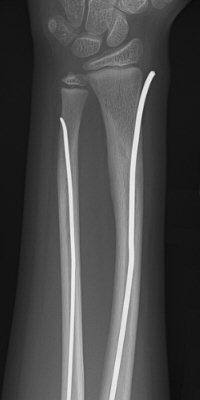

Monteggiafraktur, opererad med TEN-spik